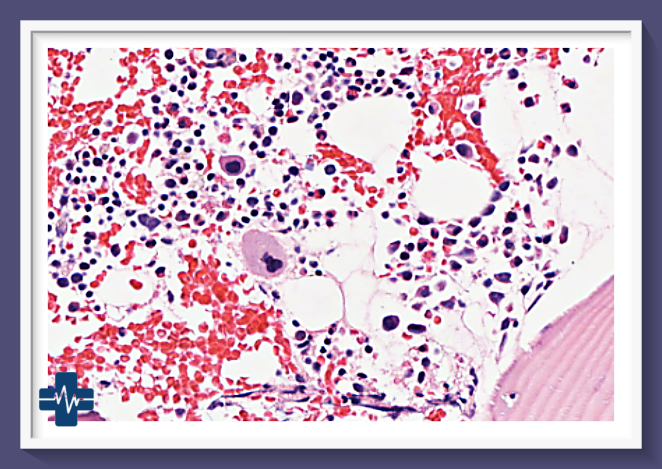

골수암, 특히 급성 골수성 백혈병(AML)과 다발성 골수종은 혈액암의 일종으로, 골수에서 비정상적인 혈액 세포의 과도한 증식이 특징입니다. 이러한 암의 치료는 복잡하며 여러 단계의 치료법이 포함됩니다. 최신 연구와 치료법의 발전에도 불구하고, 골수암은 여전히 높은 도전을 요하는 질환입니다.

골수암은 혈액암의 한 유형으로, 주로 골수에서 발생하는 암을 말합니다. 이 암은 급성 골수성 백혈병(AML), 만성 골수성 백혈병(CML), 다발성 골수종 등 다양한 형태로 나타납니다. 각각의 형태는 고유한 증상과 치료 방법을 가지고 있으며, 이는 진단과 치료 전략에 중요한 정보를 제공합니다.

골수암의 조기 발견은 중요합니다. 혈액 검사를 통해 빈혈, 백혈구 수치의 변화, 혈소판 감소 등을 확인할 수 있으며, 이는 조기 진단에 도움을 줍니다. 또한, 골수 검사를 통해 암세포의 존재와 유형을 파악할 수 있습니다.